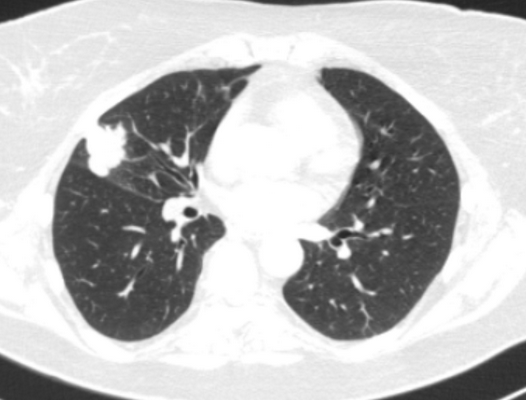

Фото 1 — Центральный рак правого нижнедолевого бронха (1) с обтурацией и метастазами (2) в бифуркационные лимфатические узлы

Периферический рак постепенно сформировывается в боковых отделах легких, медленно прорастая и ничем себя не обнаруживая. Данная опухоль легкого симптомы долгое время может не давать, они появляются при значительном местном распространении, вовлечении соседних органов и структур, прорастания бронхов. Диагностика рака легких этого типа локализации чаще всего возможна при профилактическом обследовании (рентгенографии или компьютерной томографии).

Фото 2 — Периферический рак (1) верхней доли правого легкого